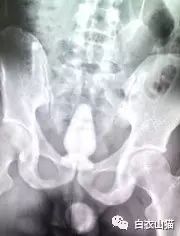

这是一个啤酒瓶。男性。

上面是一个啤酒瓶在大肠里。病人是男性。这是常见的肛门内异物。

这种情况,往往只要给病人打上全身麻醉,肛门松弛后,就可以用卵圆钳经过肛门把啤酒瓶拉出来。